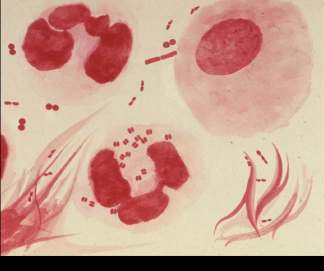

Staining Methods

Direct Sample Staining: Used for rapid diagnosis (e.g., Gram stain of cerebrospinal fluid).

Cultured Organism Staining: Includes capsule stain (for visualizing capsules, a virulence factor) and Giemsa stain (for blood parasites and fungi).